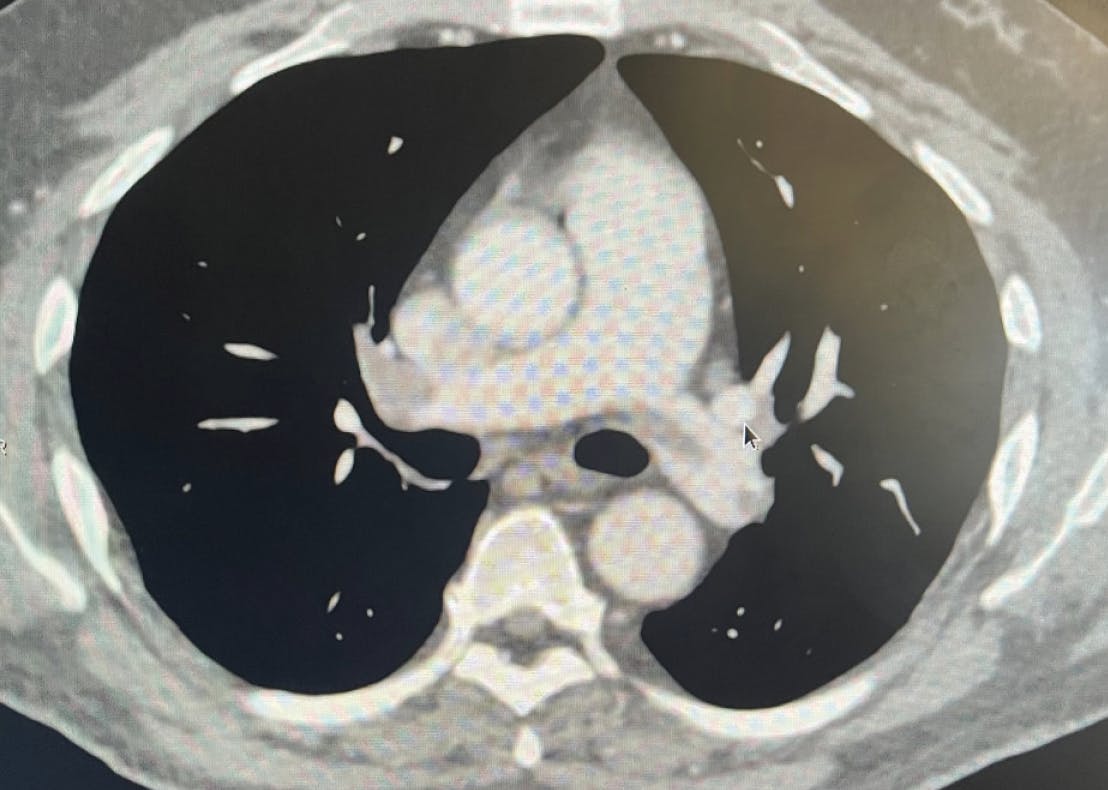

A patient in his late 50s presented to the emergency department (ED) with fatigue, shortness of breath, and emesis. The patient had previous medical history of hypertension, diabetes, and anemia. Initial diagnostics showed elevated levels of high-sensitivity troponin I at 482.8 ng/L, a HR of 104 bpm, and oxygen saturation of 91%. A transthoracic echocardiogram revealed mildly dilated RV size with mildly reduced ventricular systolic function. Evaluation of imaging and diagnostics confirmed a submassive saddle PE with right heart strain due to an RV/LV ratio of 1.9 (Figure 1, Figure 2, and Figure 3). The decision was made to pursue mechanical thrombectomy with Lightning Flash for the acute submassive PE.

Figure 1. CTPA showing a submassive saddle PE.

Figure 2. Initial angiogram.

Figure 3. Preprocedural venogram.

INTERVENTION

Access was obtained in the right femoral vein. The mean PA pressure before thrombectomy was 29 mm Hg. CTPA revealed acute bilateral PE in the bilateral lobar and main PAs (Figure 1). Thrombectomy was performed with the 16-F Lightning Flash device and resulted in < 50 mL of blood loss. A postprocedure pulmonary angiogram revealed successful mechanical thrombectomy with establishment of flow from the PAs to both lungs (Figure 4 and Figure 5). The patient’s HR decreased to 81 bpm, and his oxygen sats increased to 100%. The patient’s final high-sensitivity troponin I levels were measured at 123.8 ng/L. With a minimal 4-day hospital length of stay and no postprocedural complications, this PE procedure with Lightning Flash was successful.